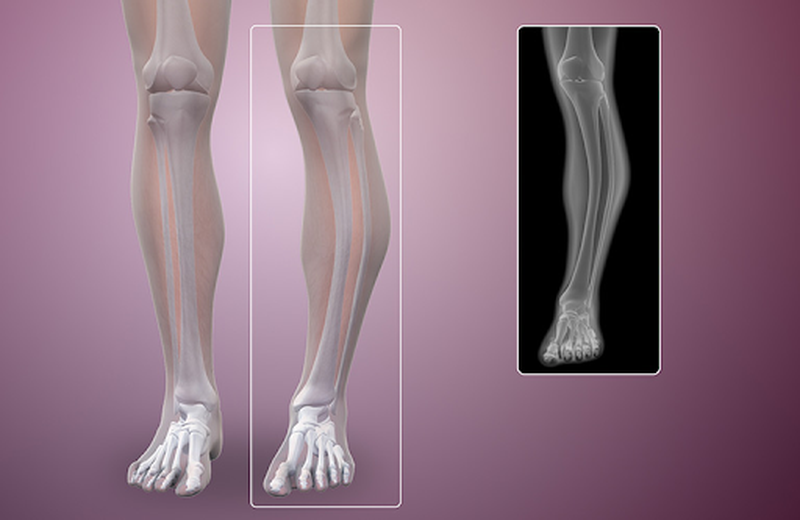

Tìm hiểu chung: Dấu hiệu của U xương ác tính 1 U xương ác tính gây hại đến cuộc sống bệnh nhân

Để nhận biết được u xương ác tính có hại như thế nào? Bạn cần nắm rõ khái niệm để dễ dàng phân biệt được chúng. Được biết, u xương ác tính là sự tạo thành của các tế bào ác tính thay vì tạo các tế bào xương mới thì cơ thể chúng ta lại tạo những tế bào ác tính tại những vị trí khác nhau của xương. Thường xảy ra ở những tế bào tạo xương và các tế bào tạo sụn, có thể di căn đến các bộ phận như phổi gây xơ phổi hay là các xương khác.